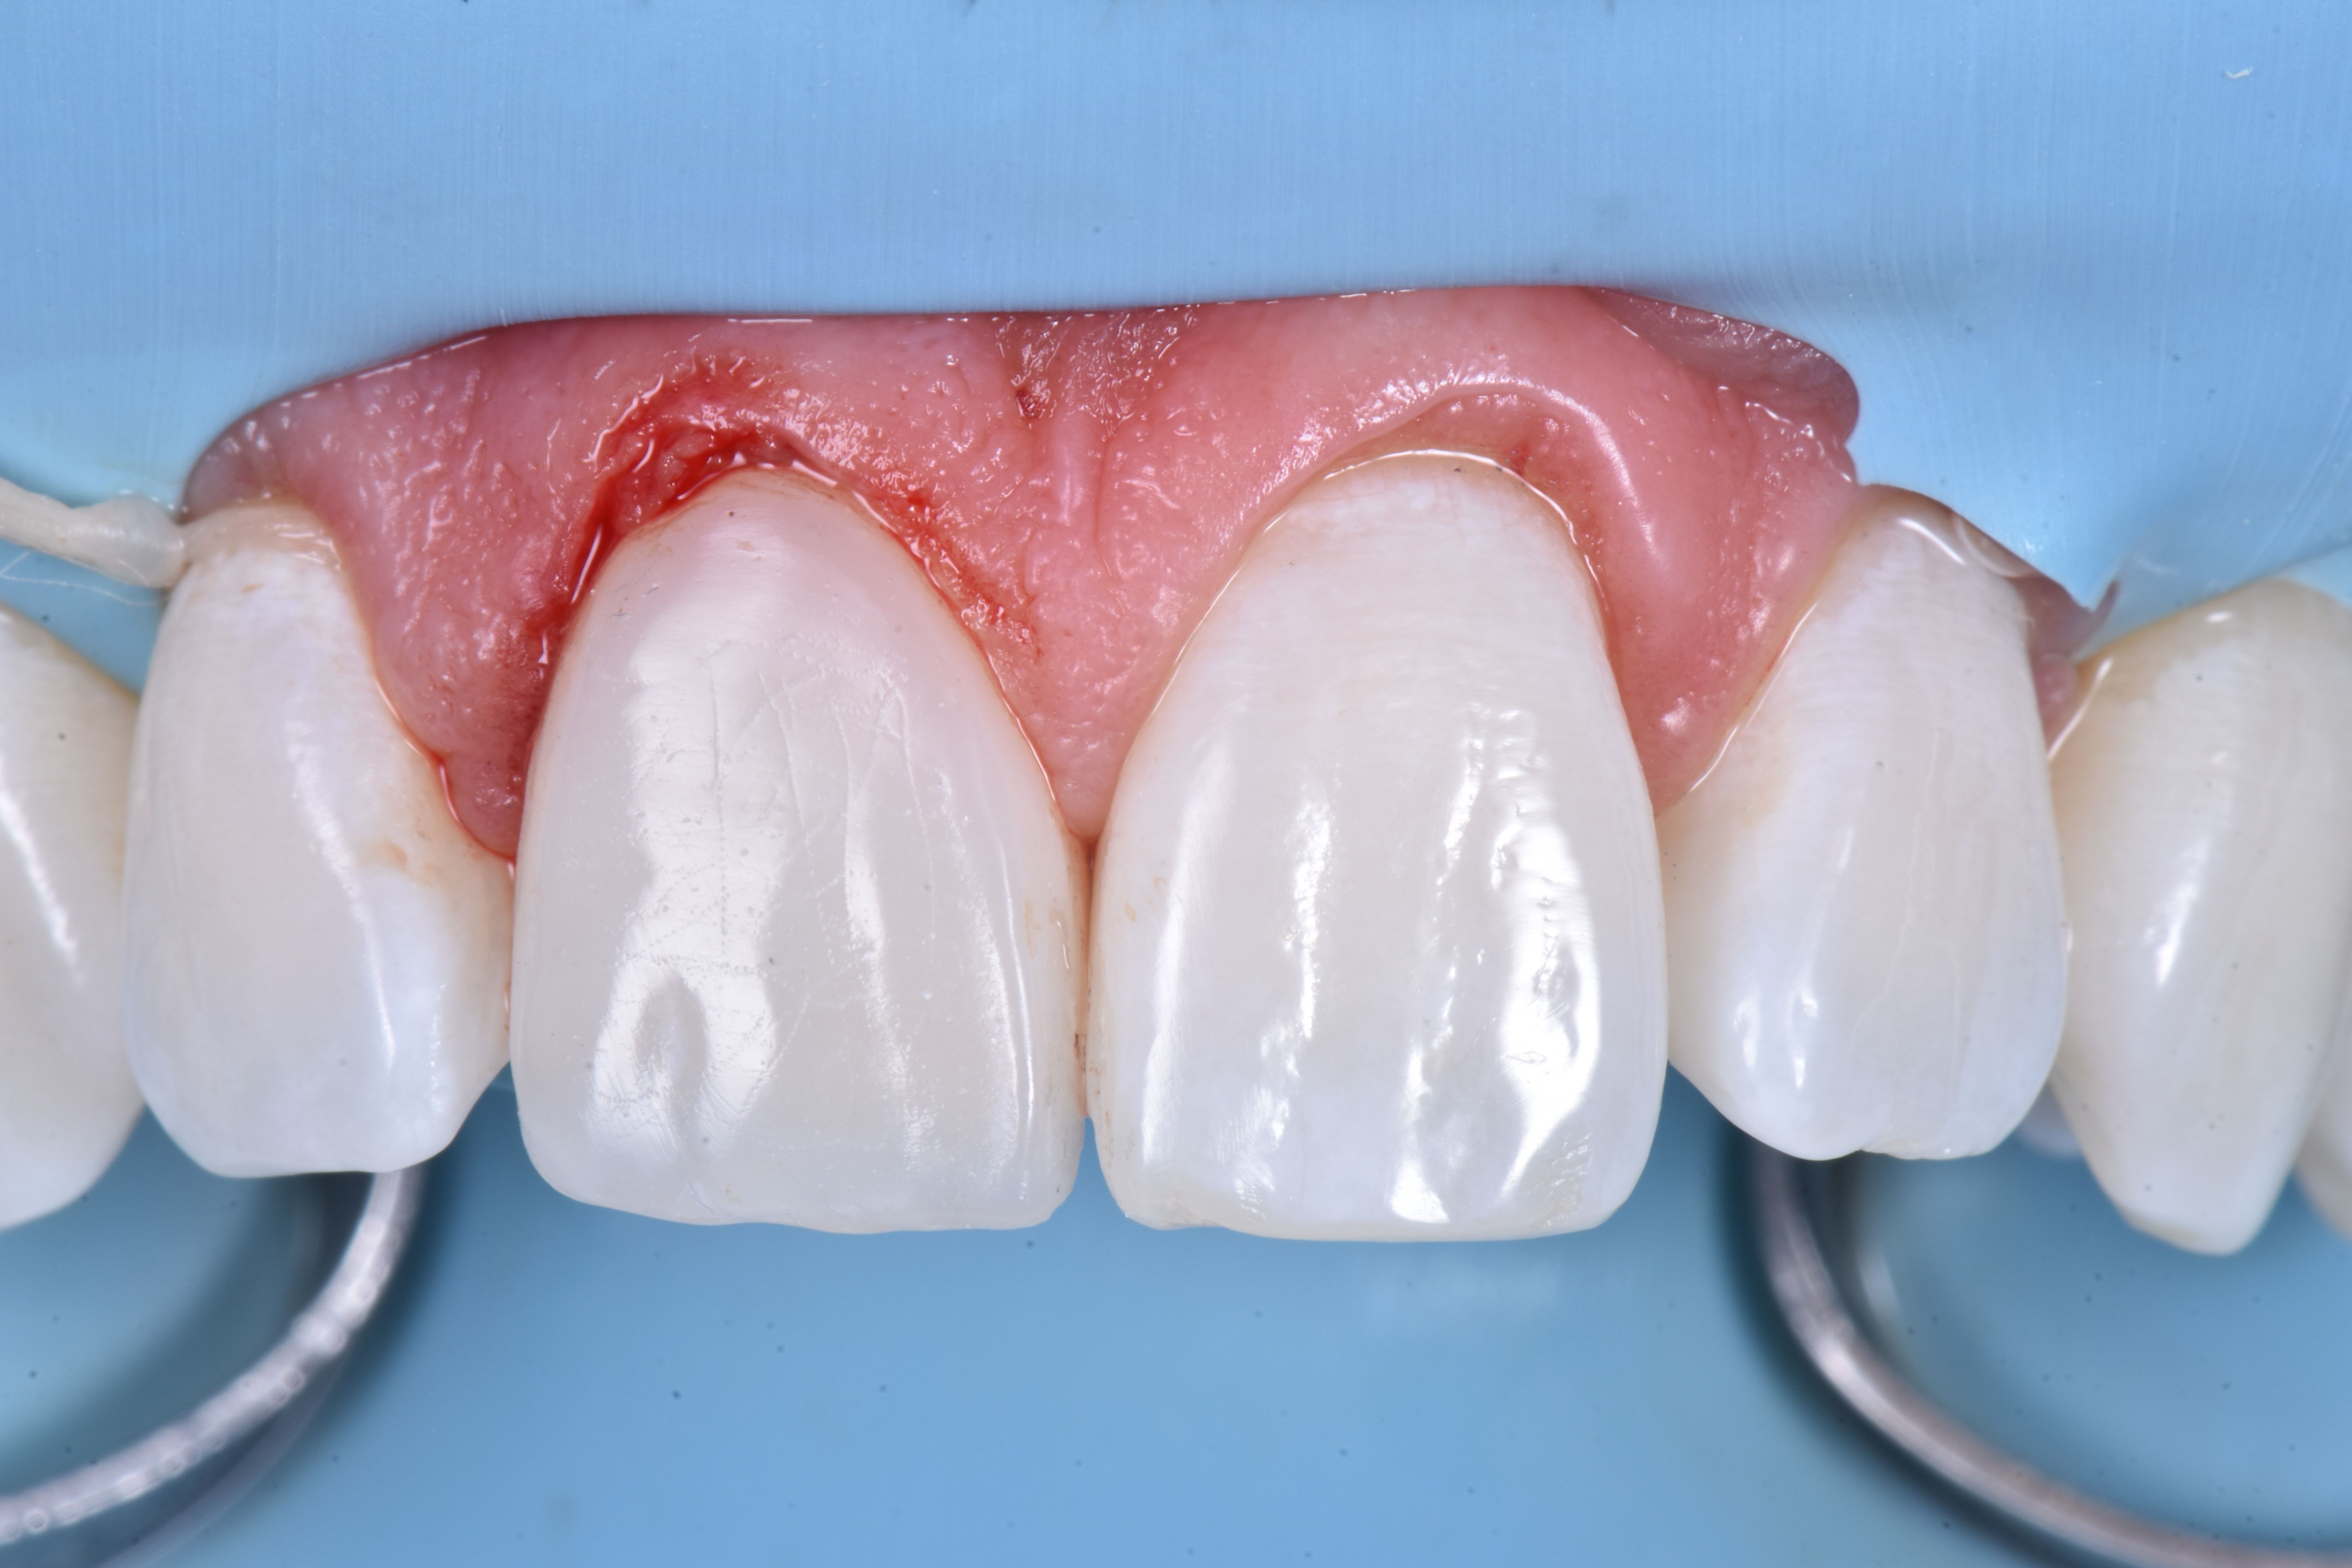

W dniu zabiegu, po wykonaniu miejscowego znieczulenia, ząb 11 odizolowano za pomocą koferdamu, rozszerzając izolację na pierwsze zęby przedtrzonowe (ryc. 4).

Następnie usunięto pękniętą rekonstrukcję kompozytową i wykonano niewielkie zukośnienie, a całą powierzchnię zęba 11 wypiaskowano tlenkiem glinu w proszku 27 μm (ryc. 5).